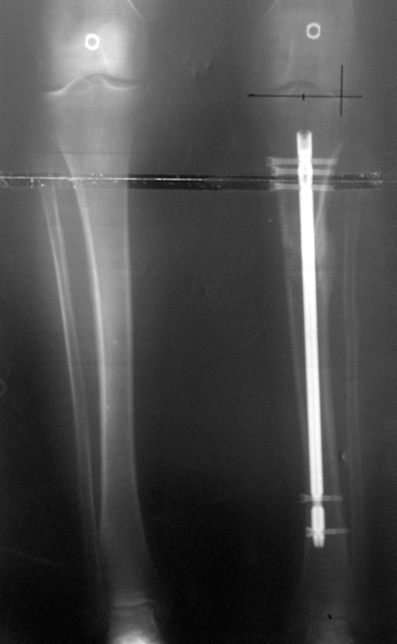

Bu Bacak Kısalık tipi bir kırığın kısalmış pozisyonda kaynaması ile oluşur. Bir çok vaka yetişkinlerde görülür ve sadece bir uzatma ile tedavi edilebilir. Ek deformiteler de aynı anda düzeltilebilir. Bu hastaların çoğu çivi üzerinden uzatma veya tam implante edilen çivi ile tedavi edilebilirler.